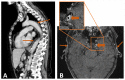

Giant cell arteritis is a medical emergency as severe, irreversible complications may occur if it is not treated in a timely manner. However, in daily practice early diagnosis can be challenging. We report the case of a 70-year-old woman who presented with multiple ischaemic cerebral vascular accidents related to newly diagnosed giant cell arteritis. Review of her charts revealed a substantial delay from the onset of symptoms to diagnosis. This case demonstrates the need for additional efforts to reduce delay in referring patients with giant cell arteritis and the need to implement fast-track clinics to prevent serious complications.